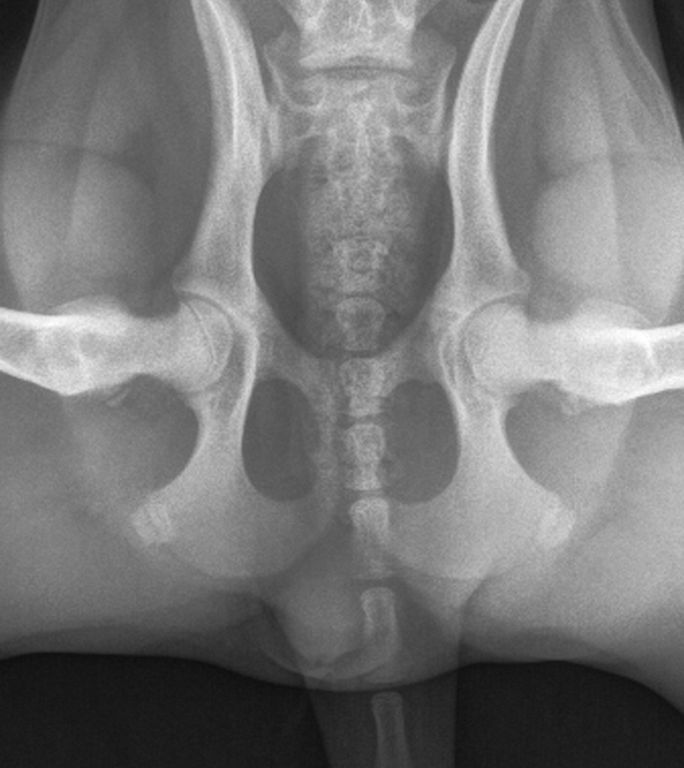

Ad oggi solo 2 medici veterinari in Italia sono abilitati ad effettuare questa metodica. Si effettuano 3 distinte radiografie (vedi foto) con il cane in sedazione.

La lettura delle radiografie viene effettuata esclusivamente dal centro di lettura PennHIP dell’Università della Pennsylvania.